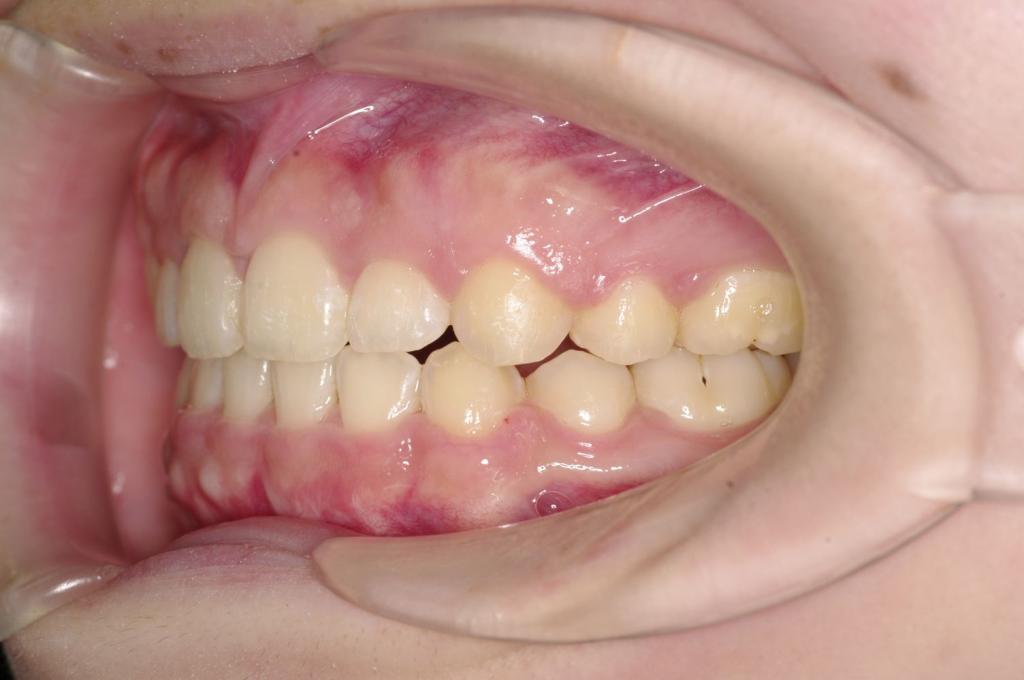

前歯、出っ歯・開咬の矯正治療

(治療期間、治療前後写真、治療方法、費用)WORKS